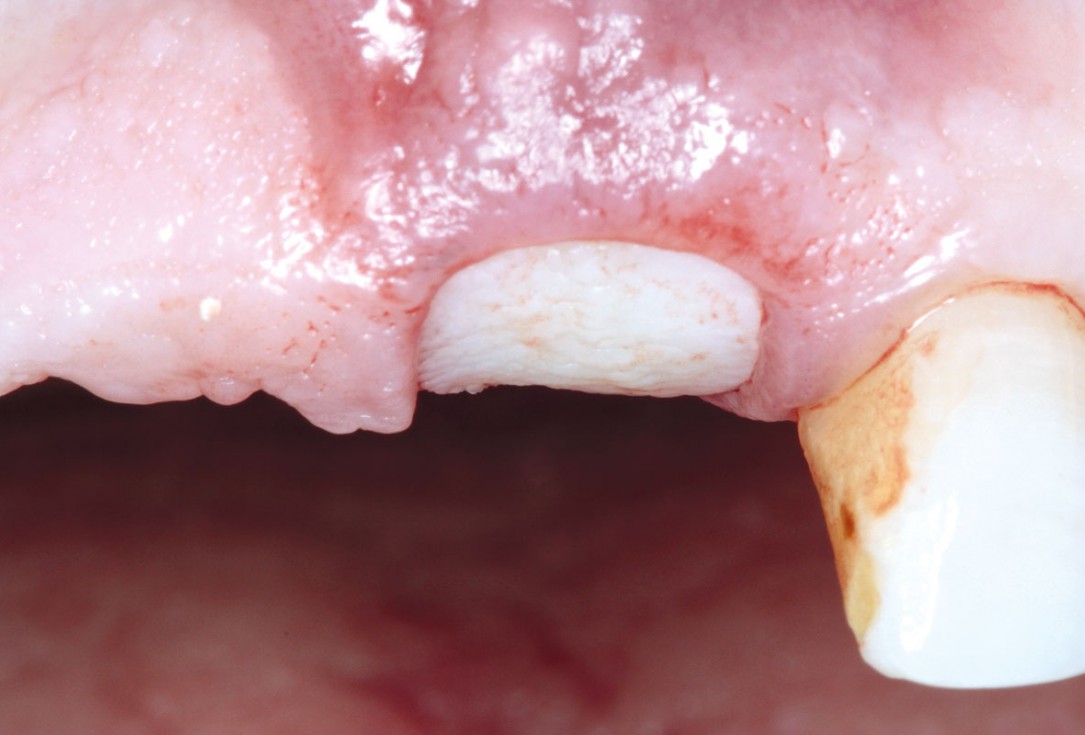

13/17 - Clinical situation 2 months post-operative.

Socket preservation using cerabone® and Straumann® Emdogain® - Dr. S. Pelekanos